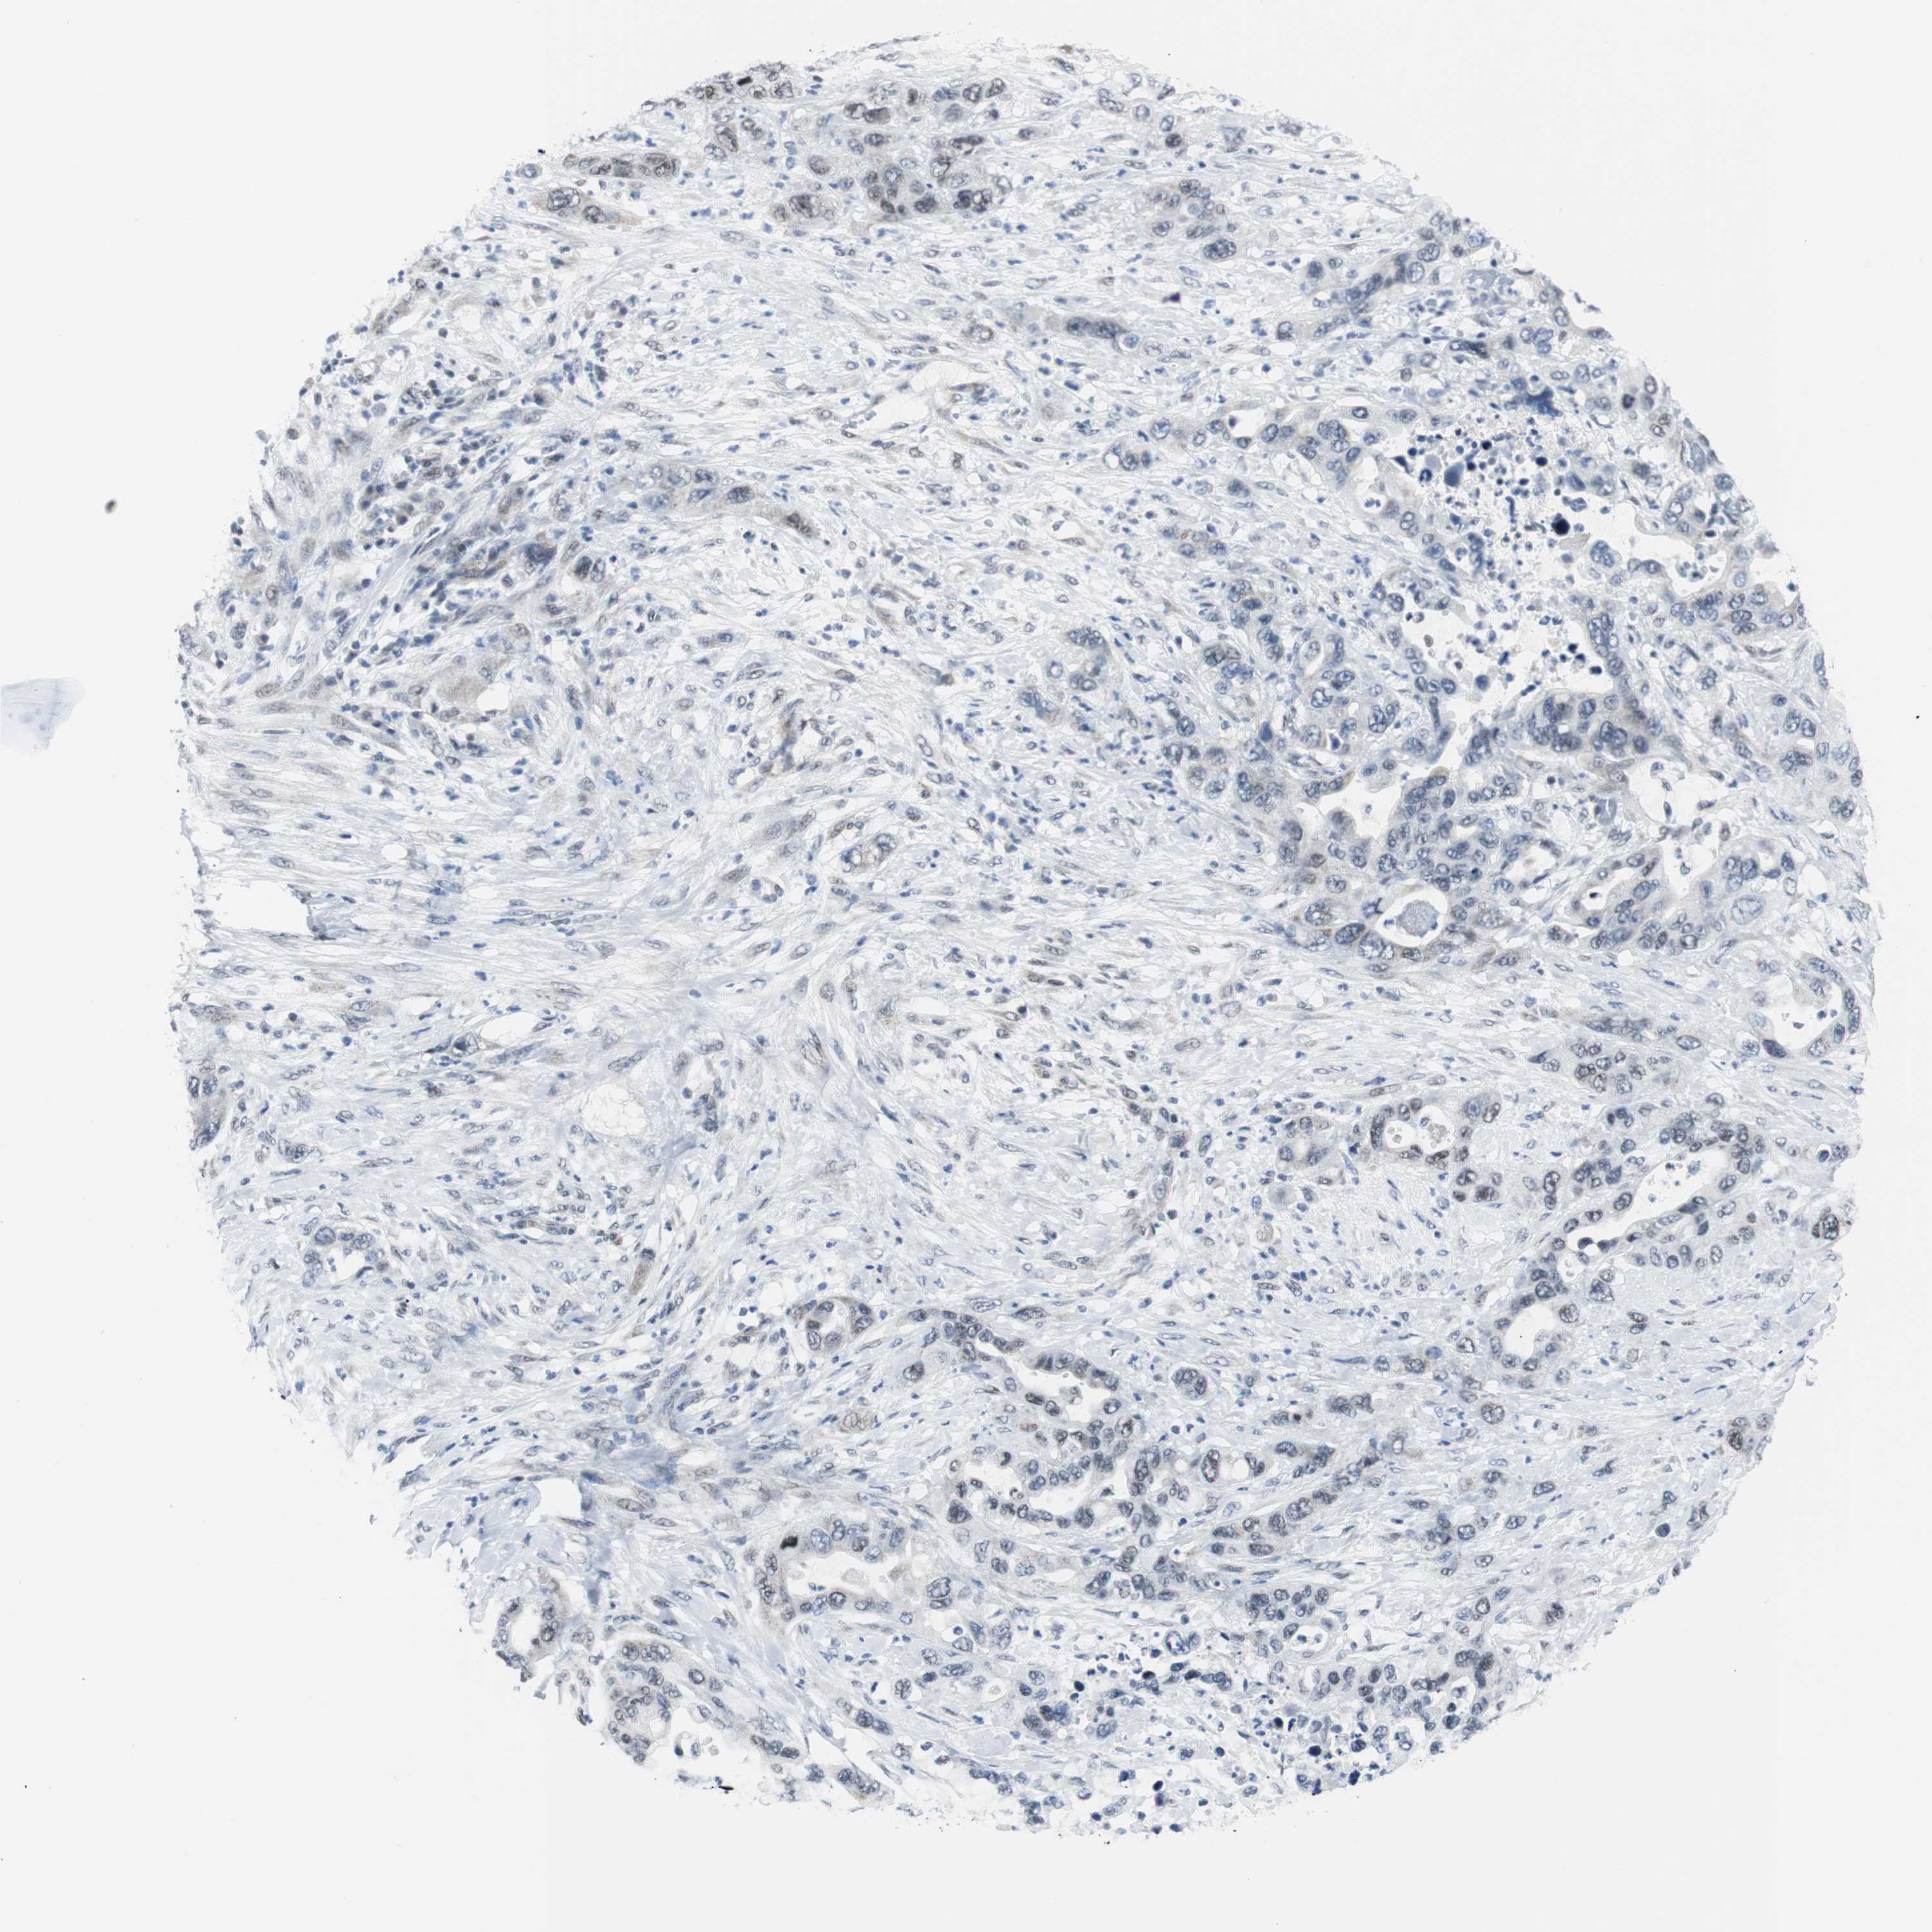

PANCREATIC CANCER - Protein expressioni

A mouse-over function shows sample information and annotation data. Click on an image to view it in a full screen mode. Samples can be filtered based on level of antibody staining by selecting one or several of the following categories: high, medium, low and not detected. The assay and annotation is described here.

Note that samples used for immunohistochemistry by the Human Protein Atlas do not correspond to samples in the TCGA dataset.

Antibody stainingi

Antibody staining in the annotated cell types in the current human tissue is reported as not detected, low, medium, or high, based on conventional immunohistochemistry profiling in selected tissues. This score is based on the combination of the staining intensity and fraction of stained cells.

Each image is clickable and will lead to virtual microscopy that enables deeper exploration of all samples and also displays staining intensity scores, fraction scores and subcellular localization as well as patient and tissue information for each sample.

Antibody HPA005544

Antibody CAB004508

Staining

High

Medium

Low

Not detected

Intensity

Strong

Moderate

Weak

Negative

Quantity

>75%

75%-25%

<25%

None

Location

Nuclear

Cytoplasmic/membranous

Cytoplasmic/membranous,nuclear

Adenocarcinoma, metastatic, NOS